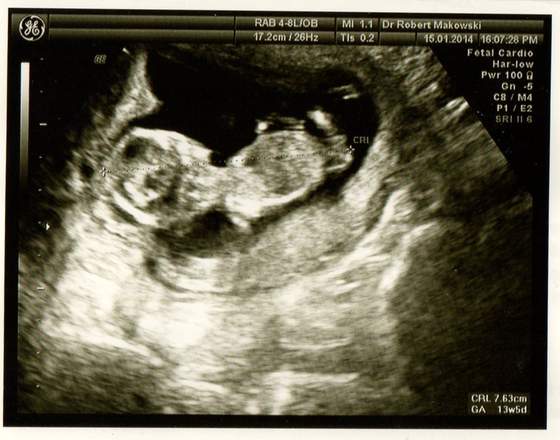

No i ja się doczekałam, Moje maleństwo ma 7,5 cm i wszystko wydaje się być ok, NT=1,8, kość nosowa jest :-) Tak się cieszę !!!!!!!!!!!!!!! A płci nie ujawniło maleństwo. Ma swoje tajemnice Zobacz załącznik 604310